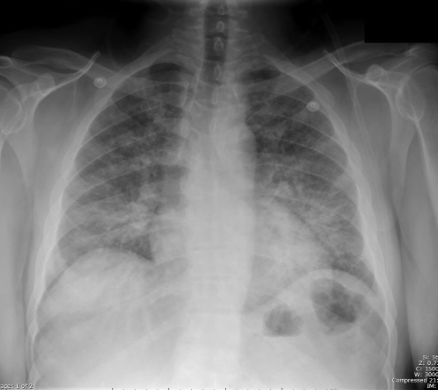

Community acquired pneumonia (CAP)

vs. Pneumocystis jirovecii pneumonia (PCP)

Diffuse bilateral infiltrates

Patchy areas of ground-glass attenuation